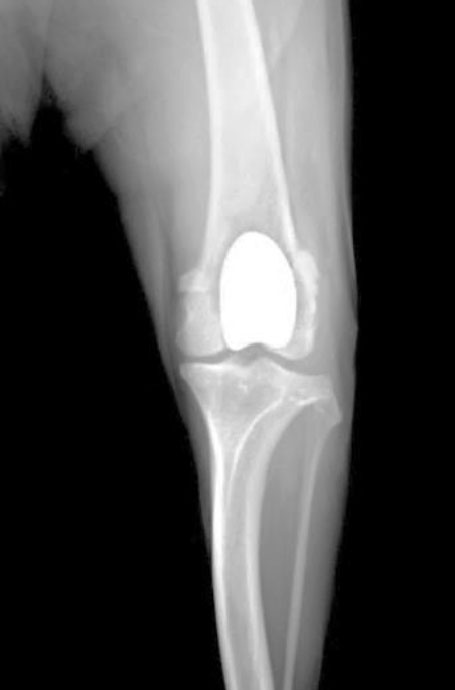

術前(膝蓋骨内方脱臼)